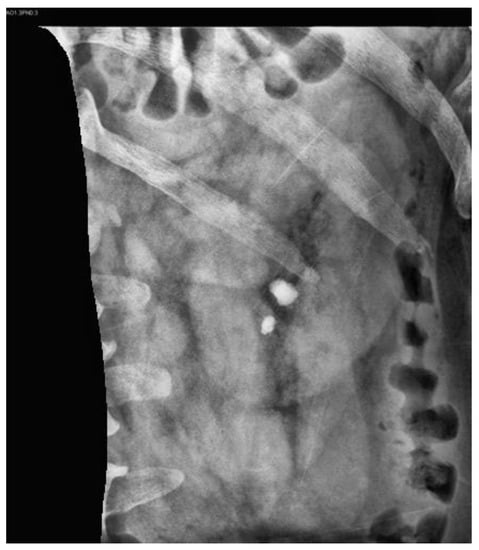

2.2. Datasets

2.3. Image Preprocessing

2.3.1. Contrast-Limited Adaptive Histogram Equalization